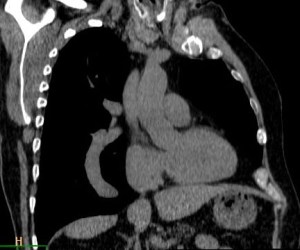

SIGNOS DE TROMBOEMBOLISMO PULMONAR

SIGNO DEL ANILLO

Signo de tromboembolismo pulmonar (TEP) en el angioTC con contraste intravenoso. El anillo (flecha) corresponde al contraste que rodea a un trombo central en un vaso cortado transversalmente. Vemos este signo en la arteria lobar inferior derecha. El signo del anillo se ve en el TEP agudo, ya que el trombo ocupa una posición central en el vaso. En el TEP crónico el trombo se hace marginal.